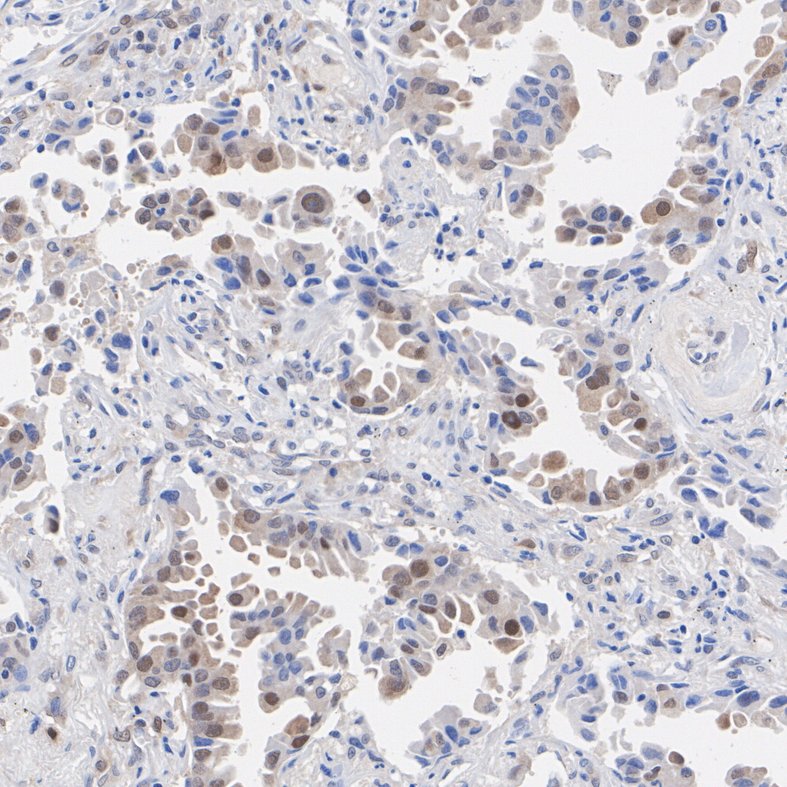

Cdk4 Recombinant Rabbit Monoclonal Antibody [SD20-42]

IHC-P